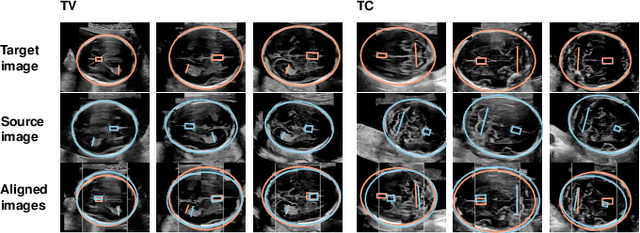

Abstract:Anatomical landmarks are a crucial prerequisite for many medical imaging tasks. Usually, the set of landmarks for a given task is predefined by experts. The landmark locations for a given image are then annotated manually or via machine learning methods trained on manual annotations. In this paper, in contrast, we present a method to automatically discover and localize anatomical landmarks in medical images. Specifically, we consider landmarks that attract the visual attention of humans, which we term visually salient landmarks. We illustrate the method for fetal neurosonographic images. First, full-length clinical fetal ultrasound scans are recorded with live sonographer gaze-tracking. Next, a convolutional neural network (CNN) is trained to predict the gaze point distribution (saliency map) of the sonographers on scan video frames. The CNN is then used to predict saliency maps of unseen fetal neurosonographic images, and the landmarks are extracted as the local maxima of these saliency maps. Finally, the landmarks are matched across images by clustering the landmark CNN features. We show that the discovered landmarks can be used within affine image registration, with average landmark alignment errors between 4.1% and 10.9% of the fetal head long axis length.